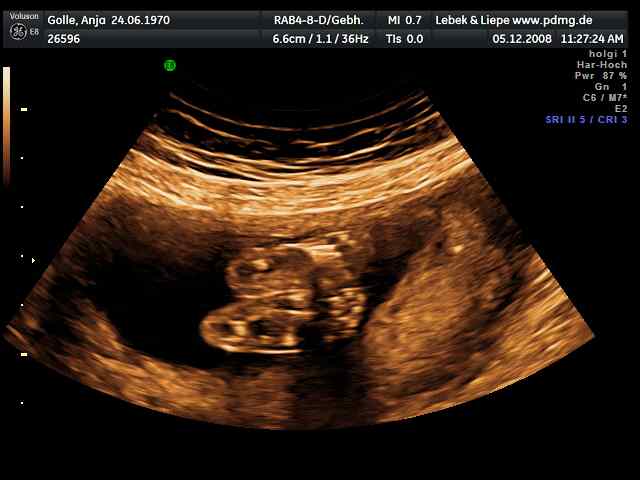

03/2006 => 1. IVM (D), POSITIV